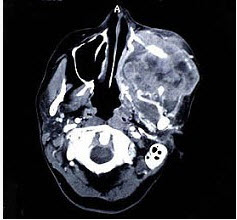

69、单项选择题

以下关于上颌窦癌(见图)的叙述,哪项是错误的()。

A.以鳞状细胞癌为最常见

B.早期无症状而不易发觉

C.肿瘤发生部位不同可出现不同临床症状(如鼻塞、复视、张口受限等)

D.早期即有明显的骨质破坏

E.远处转移较少见